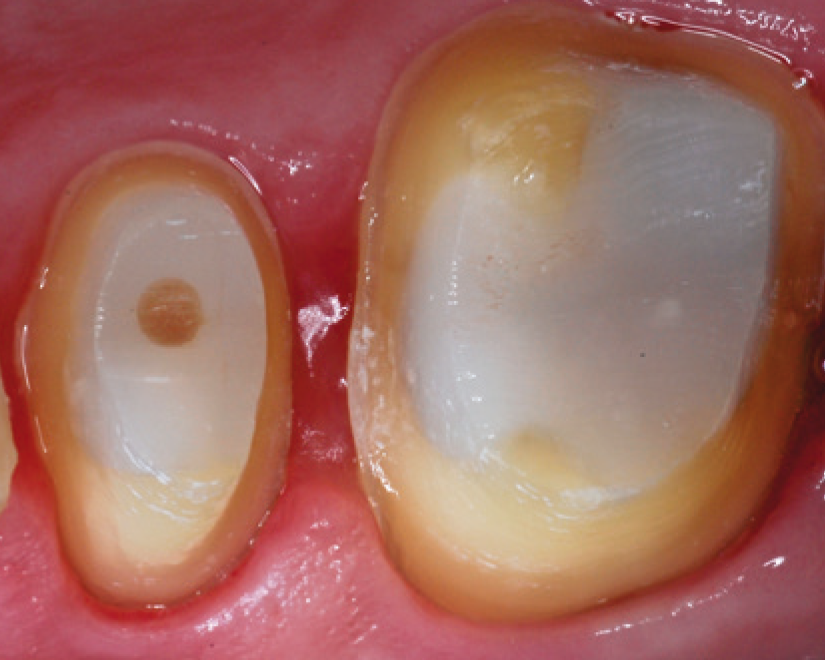

"SDR® Plus Bulk Fill Flowable ensures a tight seal of the endodontic access cavity – an important factor for long-term endodontic treatment success."

Prof. Dr. Schirrmeister, University of Freiburg, Germany

SDR® Plus Bulk Fill Flowable can be used in a variety of indications including Class I, II, III and V, primary posterior dentition, pit and fissure sealing and core build-up.

SDR® Plus is a self-leveling, bulk-fill flowable composite with low shrinkage stress that is designed to simplify the process of filling posterior Class I and II cavities. This cutting-edge composite material allows the placement of gap-free restorations, is easy to use, and minimizes shrinkage stress to make sure the material stays adapted during light curing.

SDR® Plus is optimized for bulk filling posterior cavities that are challenging to access during a dental treatment. Unlike conventional filling materials, it is flowable and can be placed in up to 4 mm increments. This allows dental practitioners to fill a large portion of the posterior cavity in just one step with a flowable material that adapts itself to the cavity walls without further instrumentation. The unique chemistry of SDR® Plus also minimizes shrinkage stress that otherwise could lead to gap formation during light curing.

SDR® Plus is indicated for a variety of dental procedures, including the filling of Class I, II, III and V cavities, pit&fissure sealing, and even core build-ups before placing a crown. It is applied in its flowable state through injection from a syringe, or a small capsule called “Compula Tip”. After placement, SDR® Plus gets light cured by the application of blue light (440 – 480 nm wavelength) from a dental polymerization light. This allows the material to create a dense molecular network and replace the tooth substrate that was drilled away as a permanent restoration.